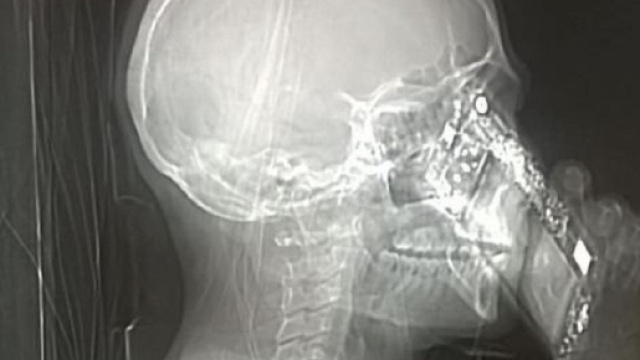

La notizia si è diffusa nel giro di poche ore, e ormai è diventata virale. Una donna, mentre veniva sottoposta ad una Tac al cervello presso l'Ospedale Cardarelli di Napoli, ha preferito non abbandonare il suo smartphone. La protagonista della vicenda, però, come riportato dal quotidiano "Il Messaggero", si è spinta anche oltre, violando una seconda regola: ha risposto ad una telefonata mentre stava per essere sottoposta all'esame.

La foto che ritrae la signora mentre, durante la Tac, tiene il cellulare accanto ad un orecchio, si è diffusa rapidamente in rete. Quando i medici si sono resi conto di cosa stesse accadendo, hanno prontamente e severamente redarguito la paziente, bloccando l'esame diagnostico.